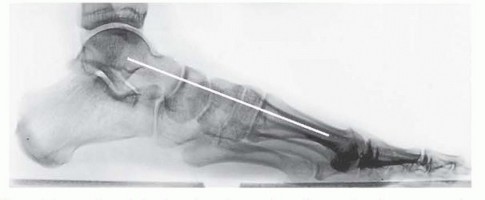

FIG 2

• Normal weight-bearing lateral radiograph demonstrating normal alignment of the medial column and the weight-bearing first ray (

white line

).